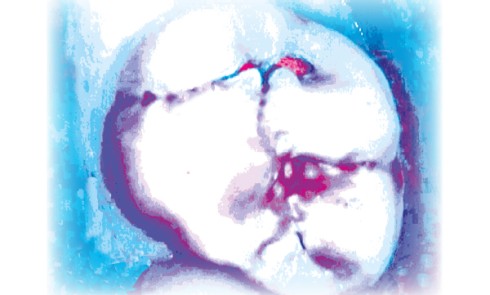

Article réservé à nos abonnés Scellements préventifs et thérapeutiques

Les scellements préventifs et thérapeutiques font partie de l’éventail des procédures cliniques appliquées à l’intervention minimale qui est le concept...